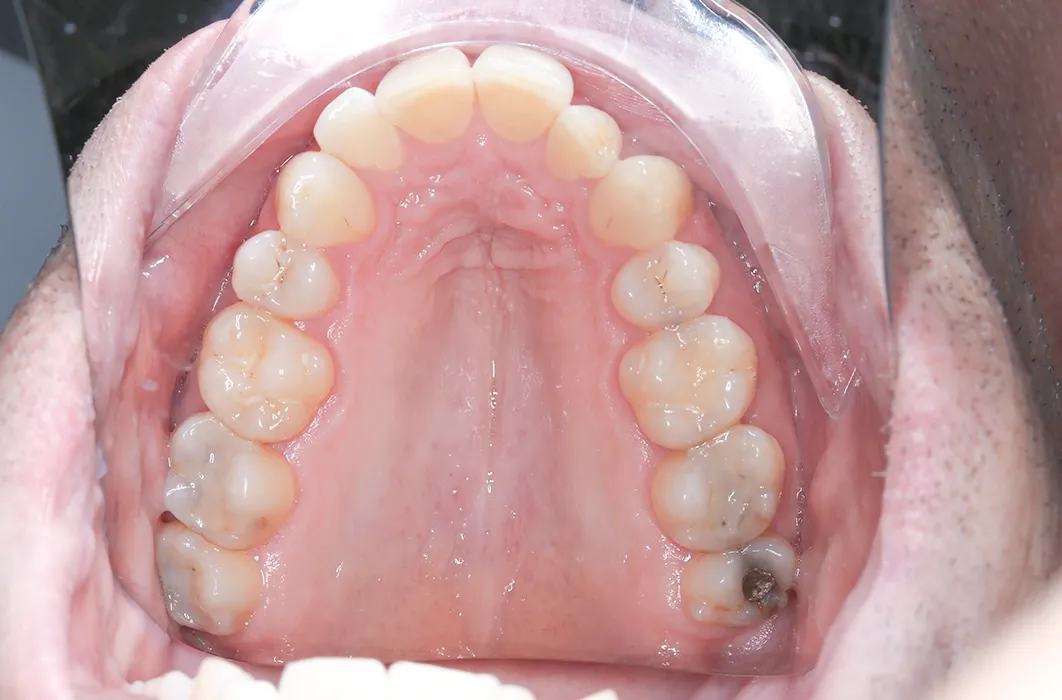

At Simply Teeth, our focus is on preserving and protecting your natural teeth. Dr Jennifer recently treated Mr C, a patient whose back teeth showed significant wear, decay, and older amalgam (silver) fillings that had started to darken and break down. These findings indicated a risk of further structural breakdown if left unmanaged.

On his first visit, Mr C’s back teeth showed:

- Plaque buildup and staining across multiple areas.

- Visible tooth wear and cavities, especially on the molars.

- Severe decay on his upper left molar (tooth 27) and lower left molar (tooth 38).

- Old amalgam fillings that had discoloured and were no longer providing full protection.

The condition of the teeth made intervention necessary to maintain stability and function.